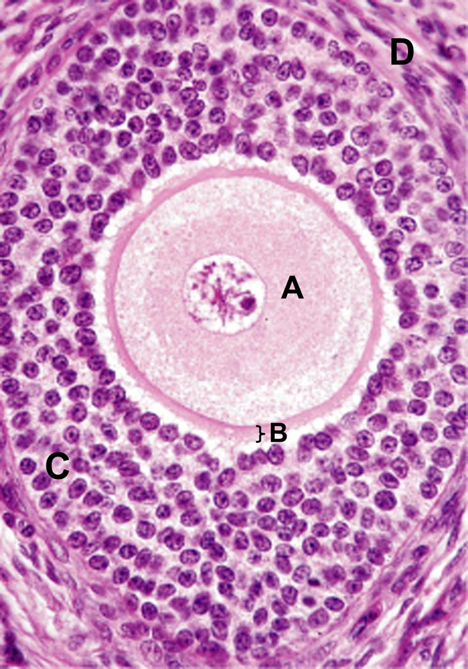

In the image below, which part of the follicle produces estrogen?

A. A

B. B

C. C

D. D

C. C

In the image below, which part of the follicle contains cells that are directly stimulated by LH?

A. A

B. B

C. C

D. D

D. D

Identify the type of follicle within the black box in the figure below.

A. primordial

B. early primary

C. late primary

D. secondary

E. Graafian

A. primordial

What is the key feature that indicates that the ovarian follicle in the image below is a late primary follicle?

A. the presence of an antrum

B. the granulosa cells are stratified

C. the clumped chromosomes in the oocyte nucleus

D. the distinct cumulus oophorus

E. the presence of the zona pellucida

B. the granulosa cells are stratified

In the image below, identify the part of the follicle that produces estrogen.

A. A

B. B

C. C

D. D

C. C